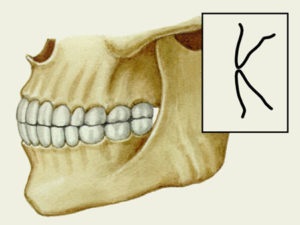

Bizonyos kiviteli a harapás rendellenes és veszélyes, mások fiziológiailag normális. Ez utóbbi kifejezés tétreharapás.

Restbite is különböznek a jobb, de ez sokkal kevésbé: például amikor progenicheskom típusú alsó állkapocs kissé kiálló, ami nem zavarja a személy. Fiziológiai vonatkozik tétreharapás: gyakran összekeverik a norma.

Normál harapás a felső fogak enyhén fedezze az alsó, közvetlen - vannak zárva élek. Emiatt az ember mosolya néz ki, nagyon látványos, lapos és széles, és az átlagos fronton elég egyértelműen.